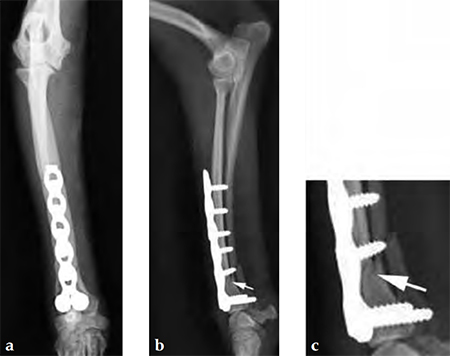

A 1-year-old female Yorkshire Terrier (1.7 kg) fractured the right distal radius and ulna (similar to a Colles fracture in humans). Open reduction and internal fixation was performed using a 7-hole 2.0 mm VET LCP notched head T-plate (a 7-hole plate was cut to eliminate the proximal two combination holes). The fracture was reduced and the distal bone fragment secured with two locking screws; the notch in the T-plate allowed independent contouring of this portion of the plate adjacent to the articulation. Compression was then applied across the fracture by loading one screw (second screw-hole proximal to the fracture); a second standard screw was then secured adjacent to the fracture (angled away/proximal to the fracture). The remaining screws were placed in a locked fashion. Despite the attempt at anatomical reduction, a slight (~1 mm) step was observed in the craniocaudal reduction (Fig 3). No fixation was applied to the ulna. A soft, padded bandage was applied to the forelimb (distal to the elbow joint) for minimal support and to control swelling.

The dog was discharged from the hospital 2 days postoperatively with instructions for strict exercise restriction; the dog was ambulatory on all four limbs at this time, although lame on the right forelimb. The bandage was to be removed in about 57 days. The dog did very well and was reevaluated 8 weeks postoperatively, at which time radiographs revealed a healed radius and atrophic ulna (Fig 4 - the ulnar atrophy is the norm in the canine for this repair in these small dog breeds). The dog was fully ambulatory and without lameness at this time; however, there was a slight decrease in full flexion at the antebrachiocarpal jointagain, this is the norm with this repair due to the surgical dissection and plate placement under the extensor tendons, which does not cause any functional deficit in the dog. The dog was gradually returned to full activity over the ensuing 2 weeks. It is recommended that these dogs not be allowed to jump from heights (eg, bed, chair) as they are at increased risk for this fracture, regarding the opposite limb in this patient.